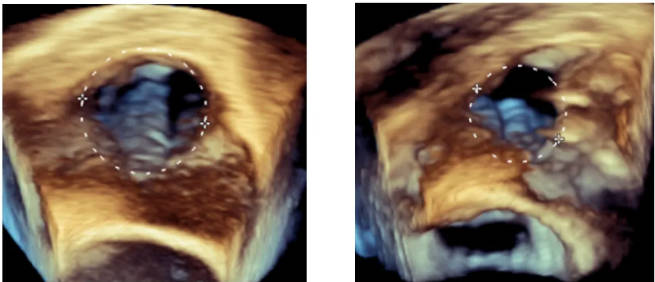

术前超声心动图示三尖瓣极重度反流

术前超声心动图示三尖瓣瓣环极度扩张致三尖瓣瓣叶对合不良

术后三尖瓣反流量明显减少,由极重度改善至中度

瓣环面积明显减少,瓣叶对合改善

上左图示术前三尖瓣环面积14.2cm²,右图示术后三尖瓣环面积7.95cm²